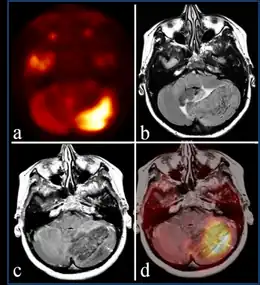

The diagnosis of the condition Lhermitte–Duclos disease can be done via the following:[4]

- Magnetic resonance image

- Positron emission tomography